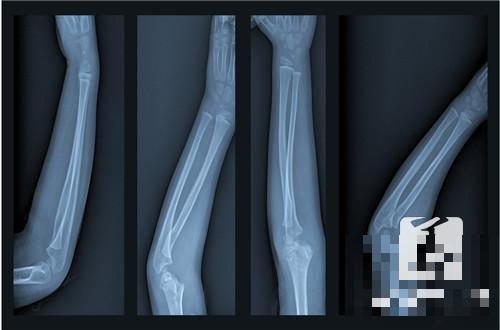

打钢钉是一种治疗方法,当患者出骨受伤比较严重的时候,就需要在手术之后打钢钉进行固定的,这样做会对骨伤的恢复有很多的帮助,当然在骨伤愈合之后,一般是在一年熬一年半左右的时候,还是需要把钢钉给取出来的,如果长时间的没有把钢钉取出来也会对身体健康造成不良影响的。